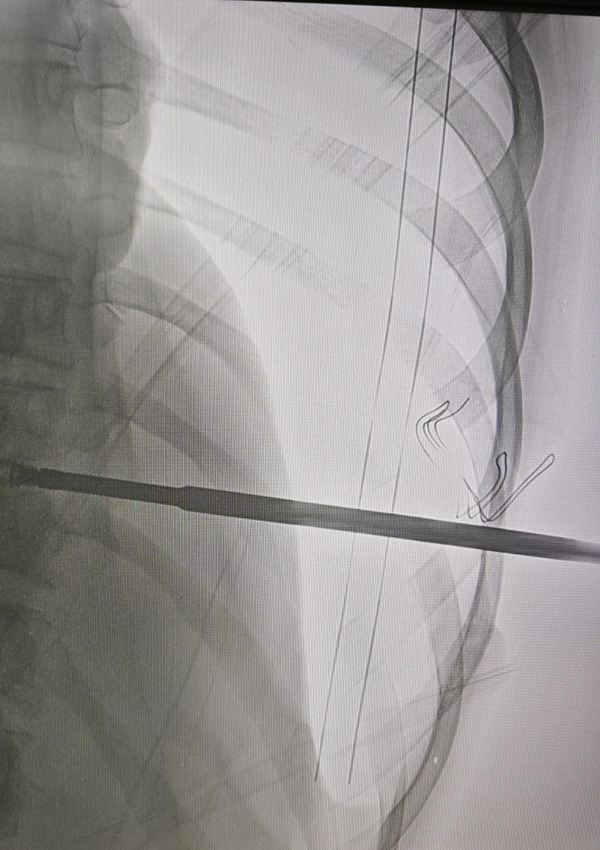

近日,北京胸科医院在复杂脊柱疾病诊疗领域再传捷报。骨科与胸外科强强联合,凭借精湛的多学科协作(MDT)模式和先进的微创技术,成功为一名胸椎结核患者实施了高难度的“胸腔镜下胸椎结核病灶清除、植骨融合术”。

面对挑战,北京胸科医院迅速启动多学科诊疗模式(MDT)。骨科脊柱专业团队与胸外科胸腔镜技术专家团队共同会诊,深入分析病情,充分发挥各自学科优势。经过严谨论证,医疗团队为患者量身定制了一套个体化诊疗方案:采用胸腔镜微创技术进行手术。该方案旨在利用微创优势,在彻底清除结核病灶、解除神经压迫的同时,最大限度地减少对胸廓与肺部功能的损伤。

手术过程顺利,医生在腔镜的辅助下,以极小的切口完成了复杂的病灶清除与植骨融合操作。术中出血少、创伤轻,达到了预期效果。更令人欣喜的是,得益于微创技术的加持,患者恢复速度显著加快。术后第3天,李某即可下床行走,大大缩短了康复周期,减轻了身心痛苦。